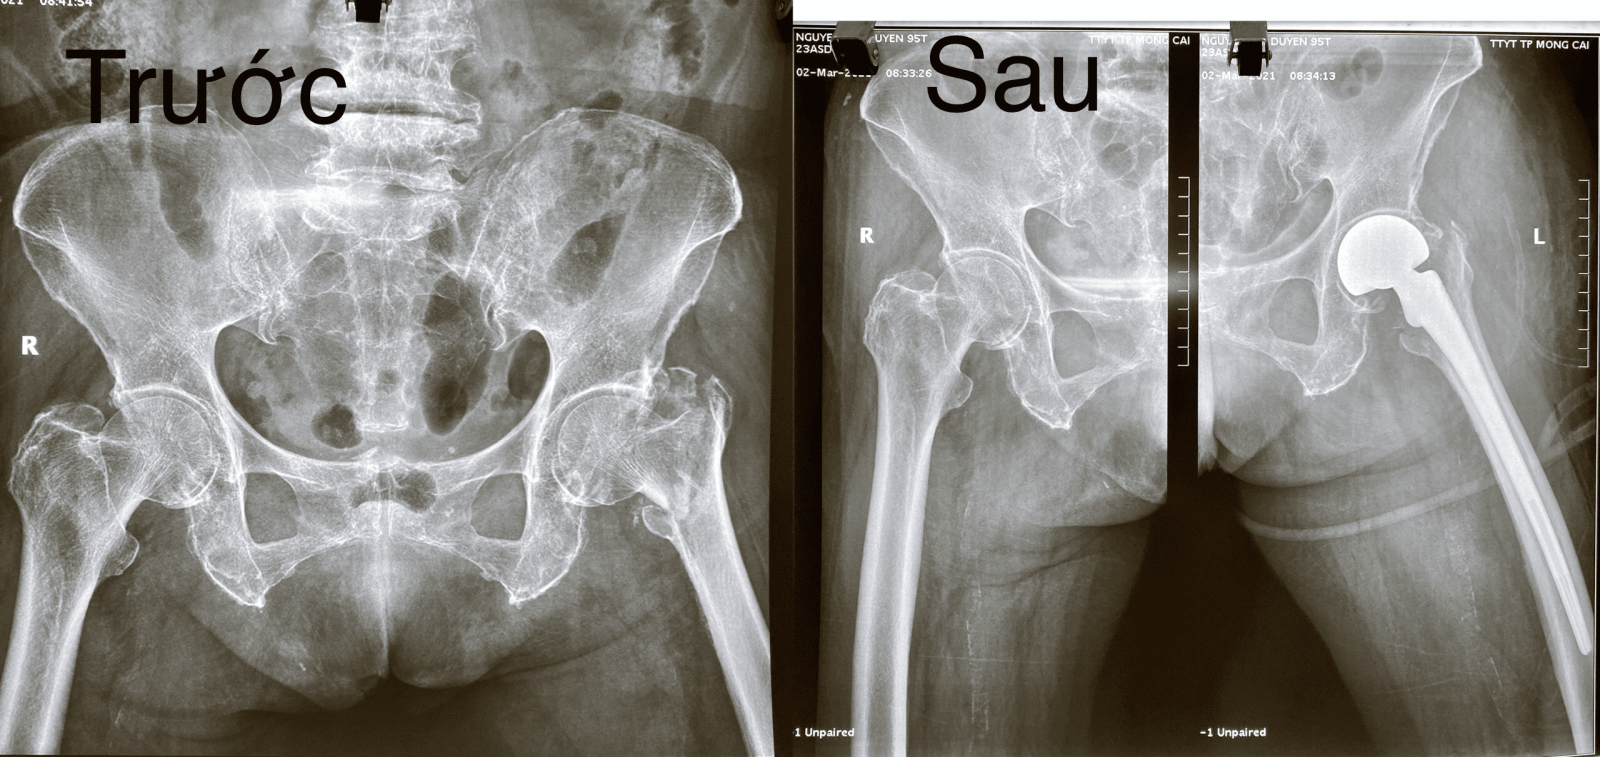

Phim X-quang chụp BN trước và sau khi phẫu thuật thay khớp háng

Ngày 01/3/2021, Trung tâm Y tế thành phố Móng Cái tiếp nhận bệnh nhân cụ bà N.T.D (95 tuổi, ND), cách đây hai tuần trước khi vào viện bệnh nhân bị trượt ngã, sau đau và mất vận động khớp háng trái.

Bệnh nhân đã dược làm các xét nghiệm, siêu âm, chụp X-quang... kết quả chẩn đoán bệnh nhân bị gãy kín liên mấu chuyển xương đùi trái và được chỉ định mổ thay khớp háng bán phần. Các bác sĩ nhận định đây là một trường hợp cần được phẫu thuật sớm giúp bệnh nhân đỡ đau, có thể cho bệnh nhân sớm ngồi dậy, tập luyện để tránh các biến chứng.